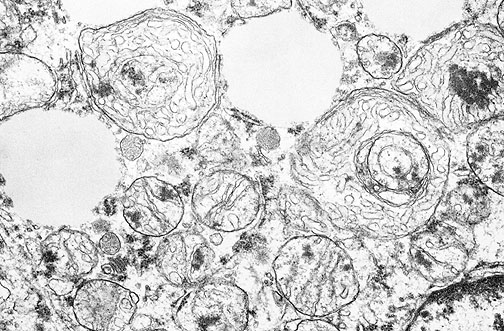

Large mitochondria with tubular cristae are seen above normal mitochondria in a cell from an adrenal cortical carcinoma in this electron micrograph.